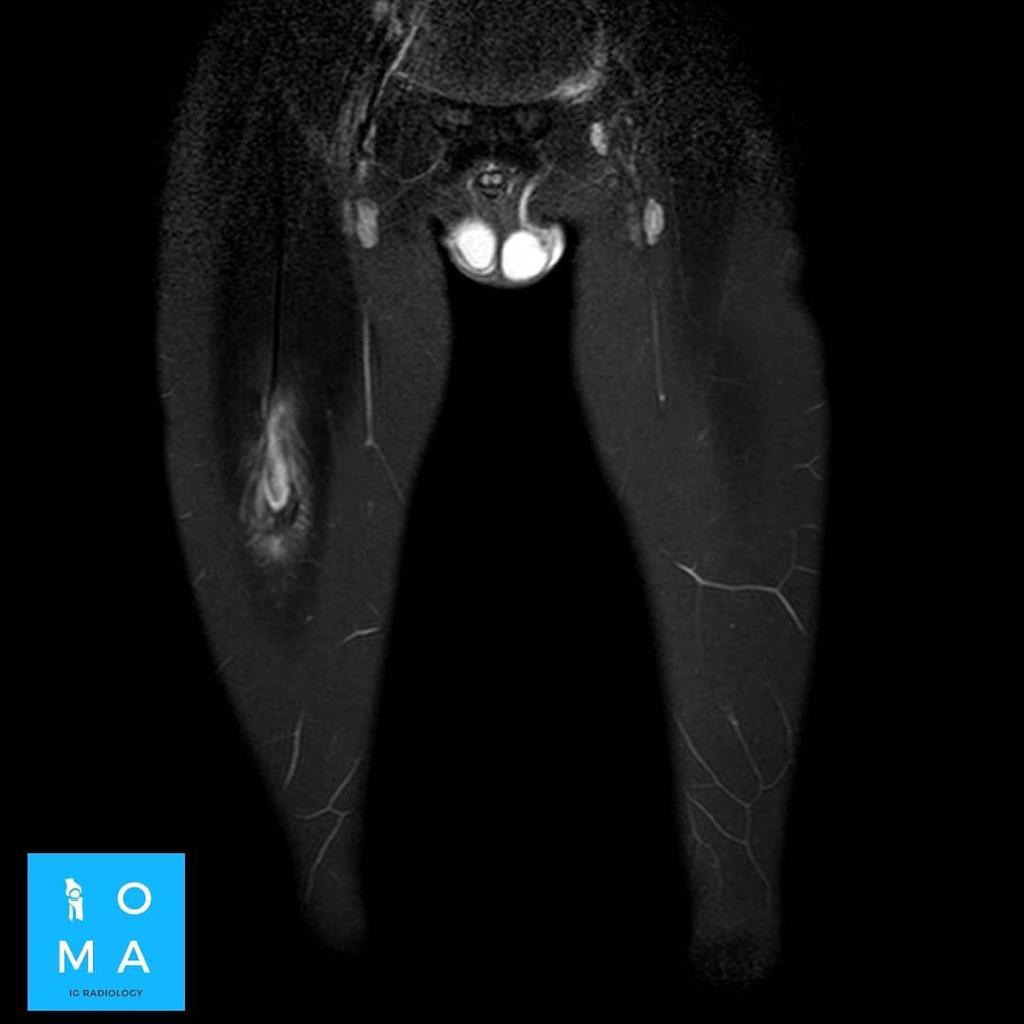

🔹Varón de 12 años que consulta por tumefacción en región anterior de muslo derecho. Refiere molestia a ese nivel 3 días antes, después de pique en partido de fútbol.

🔹Cambios inflamatorios asociado a edema y banda líquida que rodea a la unión miotendinosa central del sector medio del músculo recto anterior del cuádriceps derecho, de 10 mm de extensión, evocador de desgarro de la unión miotendinosa grado II.

🔹DESGARRO DEL RECTO FEMORAL

.El más frecuente en el grupo cuadricipital en desgarrarse. Segundo después del isquiotibial en MMII.

.La sintomatología es poco clara, la RMN aporta información fundamental acerca de la extensión y localización (lesiones cercanas a la inserción requieren mas días de tratamiento) , sin embargo el edema sobredimenciona la lesión, por lo que el método de elección, para clasificar el grado, es la ecografía realizada por un especialista en aparato osteomioarticular.

.El mecanismo principal es hiperextensión de la cadera con flexión de la rodilla.